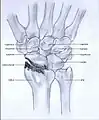

Post-traumatic osteoarthritis can be classified into four stages.[1][6] These stages are similar between SLAC and SNAC wrists. Each stage has a different treatment.

- Stage II: the osteoarthritis is localized in the entire radioscaphoid joint.

Stage II